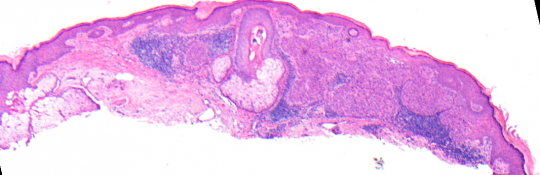

VA9: Left Forearm, Squamous Cell Carcinoma, Invasive